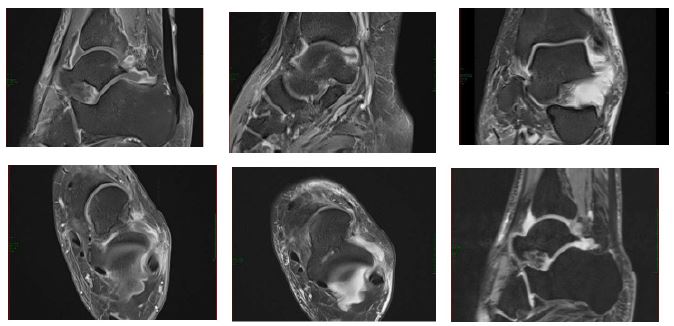

X-rays of the chest, pelvis, and femur showed a normal chest X-ray, bilateral osteoarthritis changes in the pelvis, and soft tissue calcification around the right hip joint, with vascular calcification also noted. A chest, abdomen, and pelvis CT with IV contrast identified a 29 x 44 x 88 mm fluid collection with internal gas locules deep to the right iliac muscle and a 22 x 38 mm fluid collection deep to the right gluteus minimums muscle (Figure 2). We decided to perform a pelvic MRI with contrast and US drainage. The patient continues to have a Fever of Unknown Origin (FUO). Subsequently, lab tests for brucellosis showed a positive titer, confirming brucellosis as the cause of his symptoms for the past four months.

Figure 2: Abdomen and Pelvis Ct with IV Contrast.

- Identified a 29 x 44 x 88 mm fluid collection with internal gas locules deep to the right iliac muscle and a 22 x 38 mm fluid collection deep to the right gluteus minimums muscle.

Figure 3: Abdomen and Pelvis MRI with Contrast.

- 3*5.8*8.6 cm ring-enhancing collection seen in the right iliac muscle with multiple gas locules, associated with diffuse oedema within the muscle and minimal surrounding fat standing.

- There’s another similar ring-enhancing collection seen in the right gluteus minimums muscle measuring 4.8*3.8*3.3 cm with minimal oedema in the muscle and minimal.

Symptomatic relief was provided with Perfalgan (1 g IV, four times daily) and pethidine (50 mg intramuscularly, three times), addressing the patient’s pain. Additionally, Prizma 4.5 IV was given four times daily, while Clexan (40 mg subcutaneously) and Lasix (20 mg were administered as part of the management strategy to prevent thromboembolic complications and manage fluid status. After identifying significant fluid collections via imaging, US was performed for drainage, followed by a pelvic MRI with contrast (Figure 3) for further investigations, which shows:

- 3*5.8*8.6 cm ring-enhancing collection seen in the right iliac muscle with multiple gas locules, associated with diffuse edema within the muscle and minimal surrounding fat standing.

- There’s another similar ring-enhancing collection seen in the right gluteus minimums muscle measuring 4.8*3.8*3.3 cm with minimal edema in the muscle and minimal surrounding fat standing.

- Diffuse oedema involving all right adductor muscle suggestion muscle strains.

- Bone marrow oedema was seen in the right iliac bone and acetabulum, likely reactive osteitis.

- Mildly distended right iliopsoas bursa with rim enhancement suggestion bursitis.

- Mild right hip joint fluid with synovial mild enhancement suggesting synovitis.

- Minimal free fluid was seen in the pelvis.